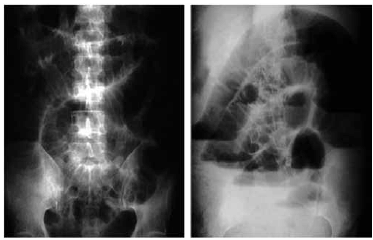

Homem de 23 anos refere dor abdominal difusa, mais intensa no hipogástrio há 3 dias, acompanhada de diminuição do apetite e náuseas. Não evacua nem elimina gases há 12 horas. Não houve melhora da dor com uso de antiespasmódico. Nega febre. Refere ter sido operado de hérnia inguinal esquerda encarcerada há 3 meses. Ao exame físico: sinais vitais normais. Abdome distendido, com presença de cicatriz operatória (12 cm) na região inguinal esquerda. RHA aumentados. Abdome doloroso à palpação superficial e profunda com descompressão brusca negativa. Realizadas radiografias simples de abdome em pé e posição ortostática (imagem demonstrada a seguir).

De acordo com dados da história clínica, exame físico e radiológico, a abordagem inicial para com o paciente deverá ser